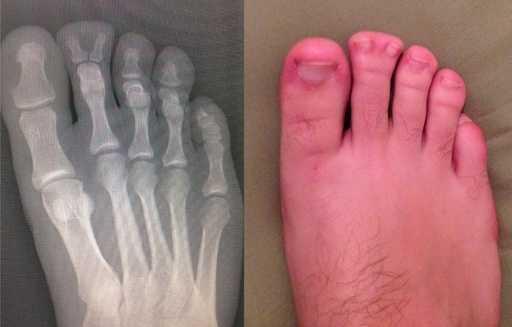

2. 这22年来,看脚指的X光是他的梦想。

一些奇怪的X光照片,看完整个人都不好了……-2.jpg